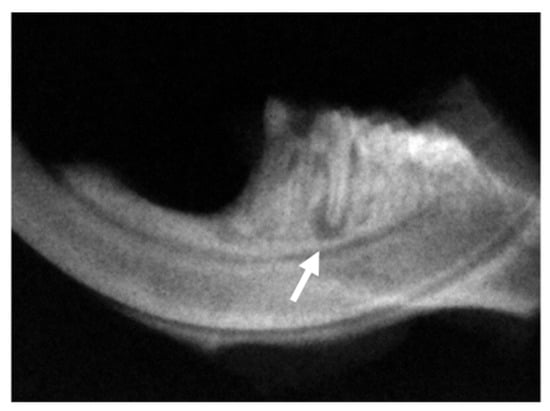

After the scintigraph assessment, the mouse mandibles were imaged after 21 days of pulpal exposure, as previously described. Radiolucency that appeared at the apex and furcation periodontium of the tooth with the exposed pulp was observed in the radiographic images (Figure 3). The radiographs were analysed using ImageJ 1.30 (Image Processing and Analysis in Java—National Institutes of Health, Bethesda, MD, USA) to quantify the amount of periapical bone loss. The periapical lesion was delimited in each image, and the area was determined in pixels.

Figure 3. Radiographic images that show radiolucency developed at the apex (arrow) and furcation periodontium of the pulp-exposed tooth of the left mandible. The image is representative from an animal of the control group.